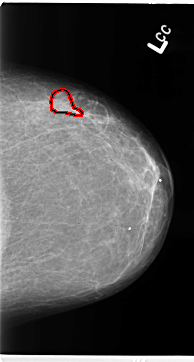

B_3099_1.LEFT_CC

LEFT_MLO LINES 4696 PIXELS_PER_LINE 2832 BITS_PER_PIXEL 12 RESOLUTION 50 OVERLAY

FILE: B_3099_1.LEFT_CC.OVERLAY

TOTAL_ABNORMALITIES 1

ABNORMALITY 1

LESION_TYPE MASS SHAPE IRREGULAR MARGINS ILL_DEFINED

ASSESSMENT 3

SUBTLETY 3

PATHOLOGY BENIGN

TOTAL_OUTLINES 1